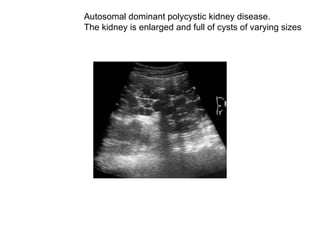

Autosomal dominant polycystic kidney disease. The kidney is enlarged and full of cysts of varying sizes